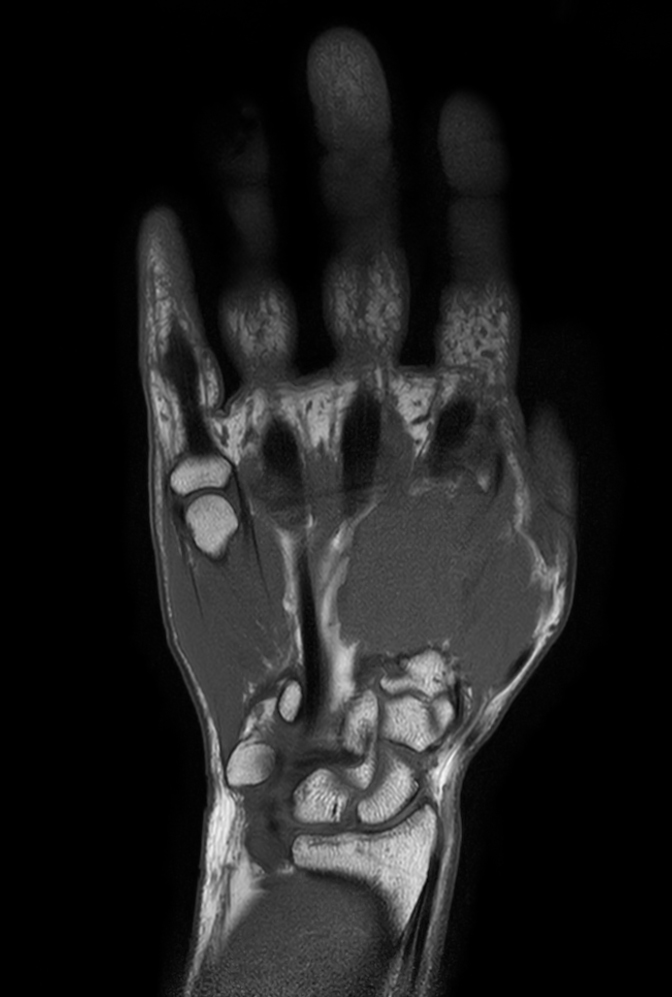

Coronal T1w TSE mDIXON XD (In Phase)